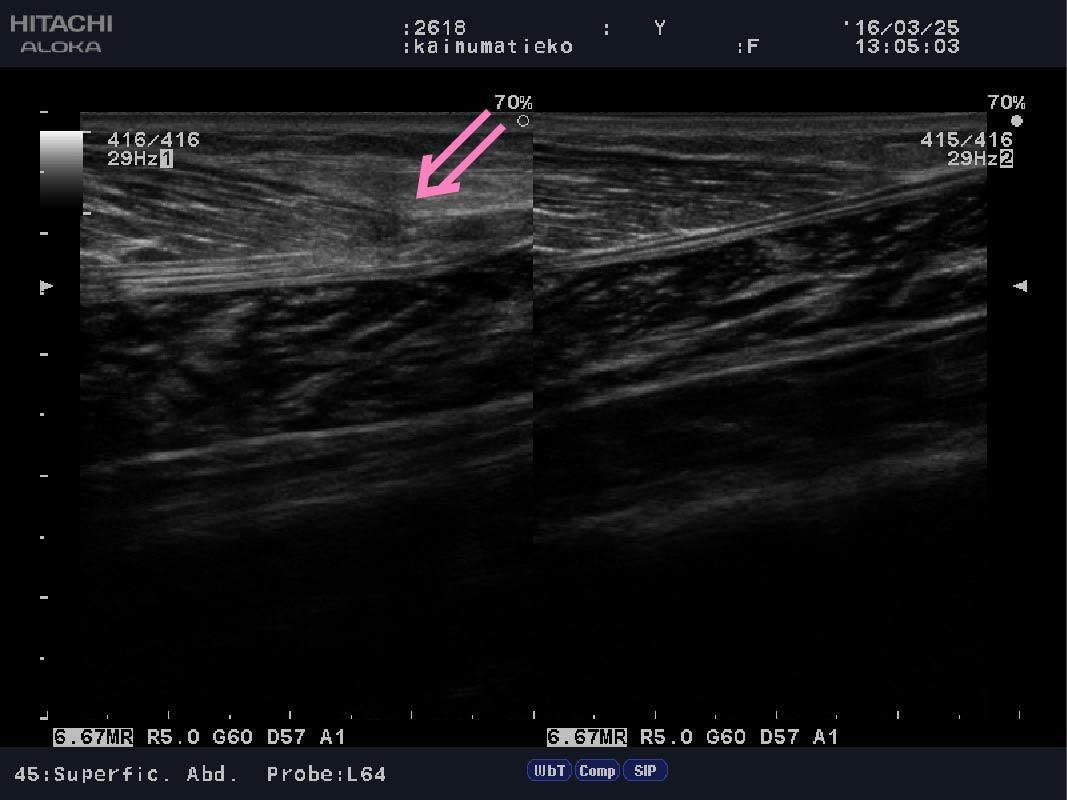

2枚目はピンクの矢印部分が損傷しております。

Calf muscle strain.jpg

こちらは受傷後からしっかり圧迫、処置ができたので、

血腫もほぼなく経過良好でございます。